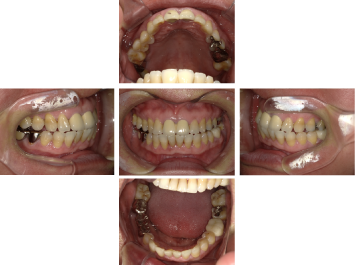

50代 女性 インプラント治療(GBR・ソケットリフト)

| 年代・性別 | 50代・女性 |

|---|---|

| 主訴 | Brの歯が取れそうなため、インプラントに変えたい。 |

| 部位 | 左下567 左上④5⑥ 右上67 |

| 治療期間 | 約3年9ヶ月 |

| 費用 | ¥3,224,500(税込) |

| 副作用・リスク |

|